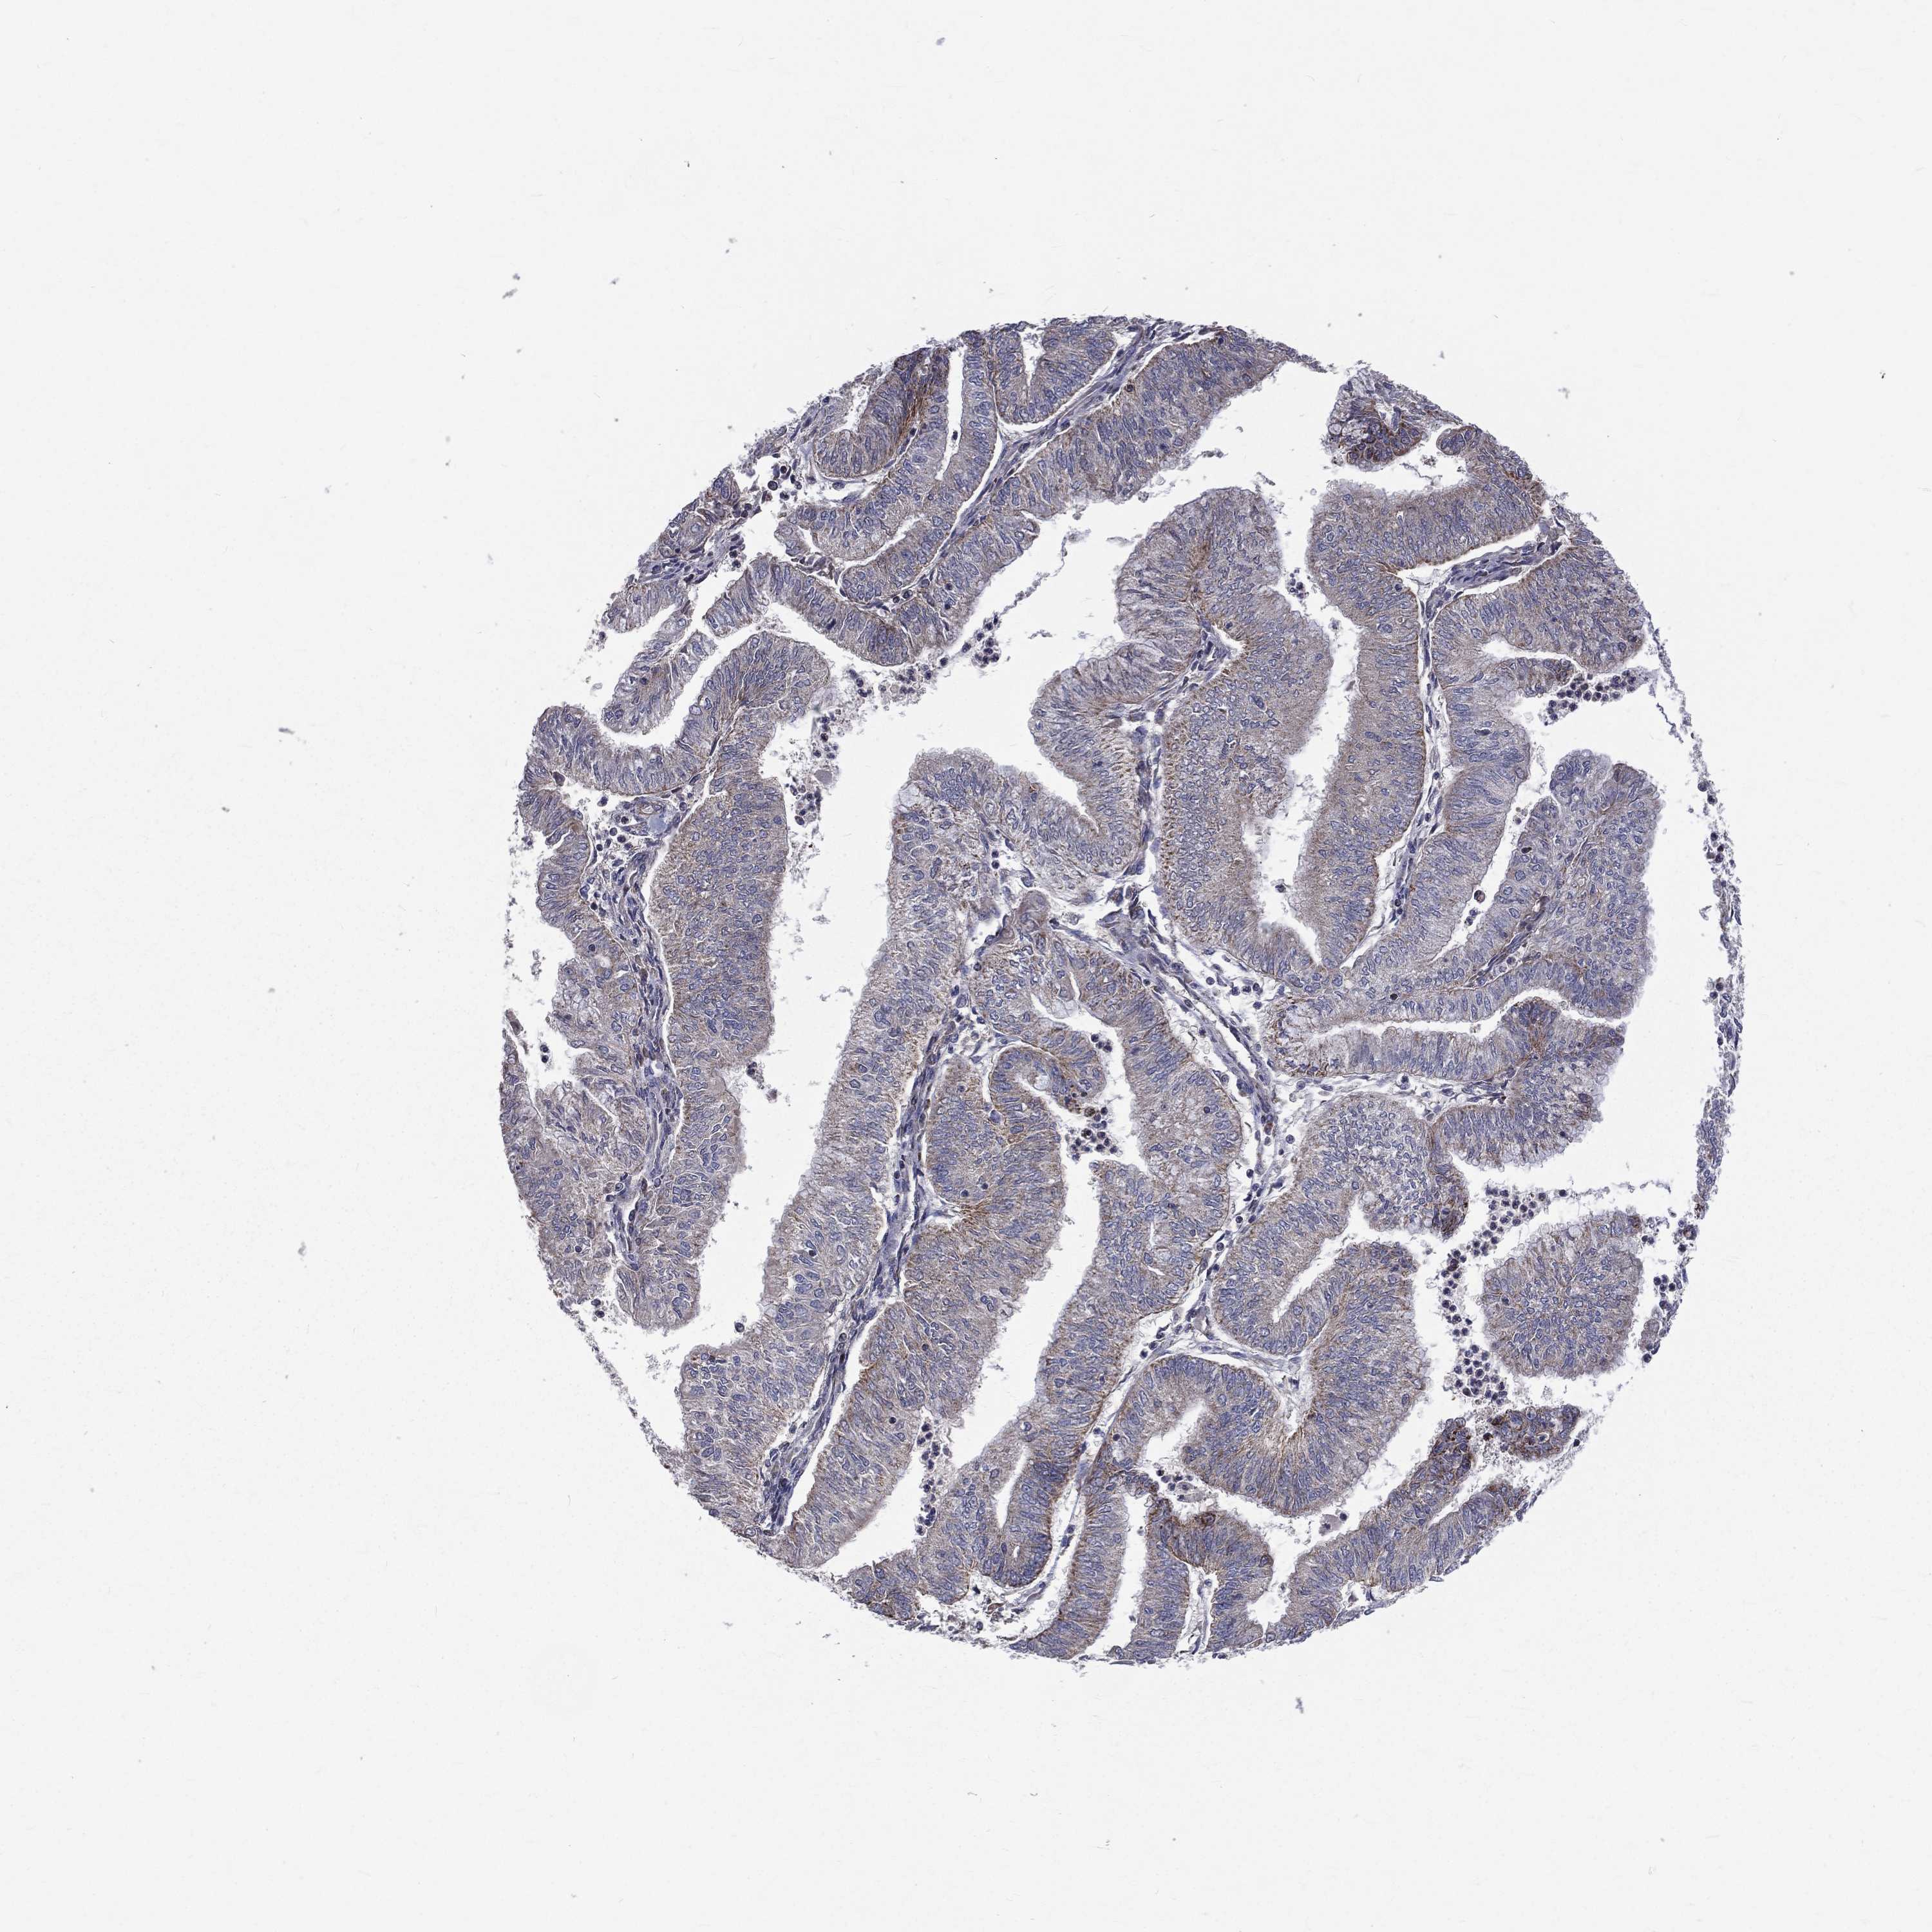

ENDOMETRIAL CANCER - Protein expressioni

A mouse-over function shows sample information and annotation data. Click on an image to view it in a full screen mode. Samples can be filtered based on level of antibody staining by selecting one or several of the following categories: high, medium, low and not detected. The assay and annotation is described here.

Note that samples used for immunohistochemistry by the Human Protein Atlas do not correspond to samples in the TCGA dataset.

Antibody stainingi

Antibody staining in the annotated cell types in the current human tissue is reported as not detected, low, medium, or high, based on conventional immunohistochemistry profiling in selected tissues. This score is based on the combination of the staining intensity and fraction of stained cells.

Each image is clickable and will lead to virtual microscopy that enables deeper exploration of all samples and also displays staining intensity scores, fraction scores and subcellular localization as well as patient and tissue information for each sample.

Antibody HPA044620

Antibody HPA058621

Staining

High

Medium

Low

Not detected

Intensity

Strong

Moderate

Weak

Negative

Quantity

>75%

75%-25%

<25%

None

Location

Nuclear

Cytoplasmic/membranous

Cytoplasmic/membranous,nuclear

Adenocarcinoma, NOS